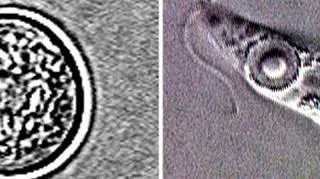

- Jej infekcja spowodowana jest przez mikroskopijną amebę, o nazwie Naegleria fowleri, która zwykle dostaje się do organizmu przez nos i dalej wędruje do mózgu. Zazwyczaj do zarażenia dochodzi u osób, które zażywają kąpieli w ciepłej, słodkiej wodzie. Nie można jednak zarazić się tym pierwotniakiem przez picie wody - powiedział rzecznik Centers for Disease Control and Prevention.

Źródło: dpd.cdc.gov